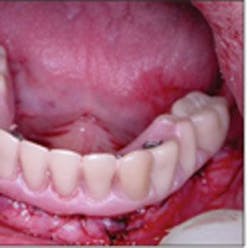

Figure 14 - Immediate delivery of the provisional fixed prosthesis at the time of dental implant placement

Upon delivery of the prosthesis to the patient, the occlusion was verified, the screws hand-tightened, and a cotton pellet and Cavit™ were placed in the access hole (Figure 14). Instructions for care and maintenance were provided to the patient with emphasis on a relatively soft diet for six to eight weeks with no parafunctional loading of the implants (Figure 15). After healing, final impressions will be made and a definitive prosthesis fabricated and delivered.